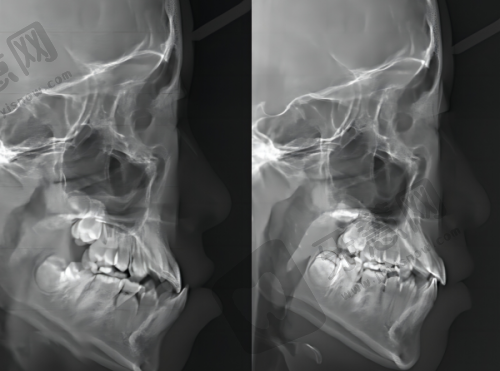

根管治疗作为治疗牙髓炎、根尖周炎等疾病的必需项目,属于深圳一档社保(职工基本医疗保险)的报销范围。不过,有一些限制条件需要注意。

首先是治疗性质要求,仅限疾病治疗类项目,像根管充填术这类就可以报销,但美容修复类,比如牙齿美白、种植牙等就不纳入报销范围。